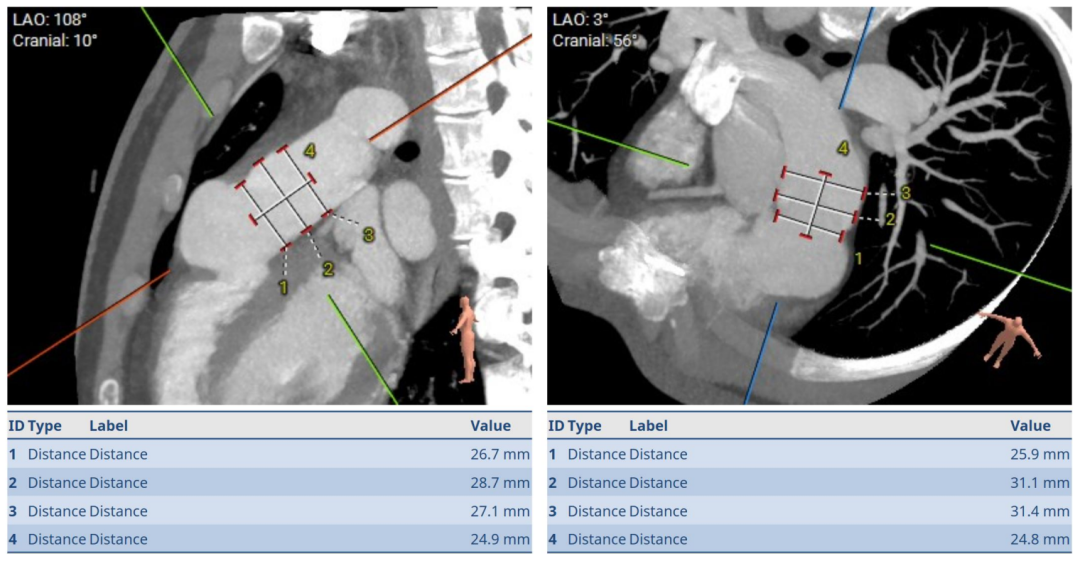

术前肺动脉CT

肺动脉瓣仅见部分瓣叶结构,主肺动脉(MPA)原窦部可见瘤样扩张,右室流出道(RVOT)结构较MPA明显扩张,整体MPA呈圆筒形。

根据术前CT、术中造影及球囊测量结果,选择P34-25型号的VenusP-Valve瓣膜,使用圈套器辅助,沿超硬导丝送输送器至肺动脉分叉处。